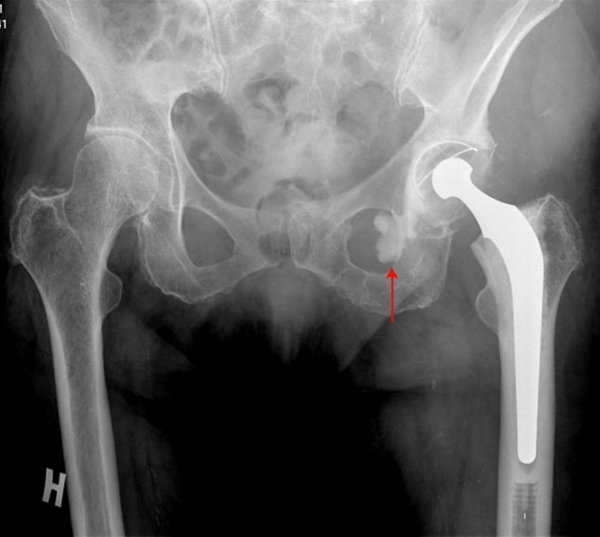

Cementeret Charnley totalprotese i venstre hofte

Cementlækage (pil) medialt fra acetabulum, der normalt ikke giver kliniske gener.